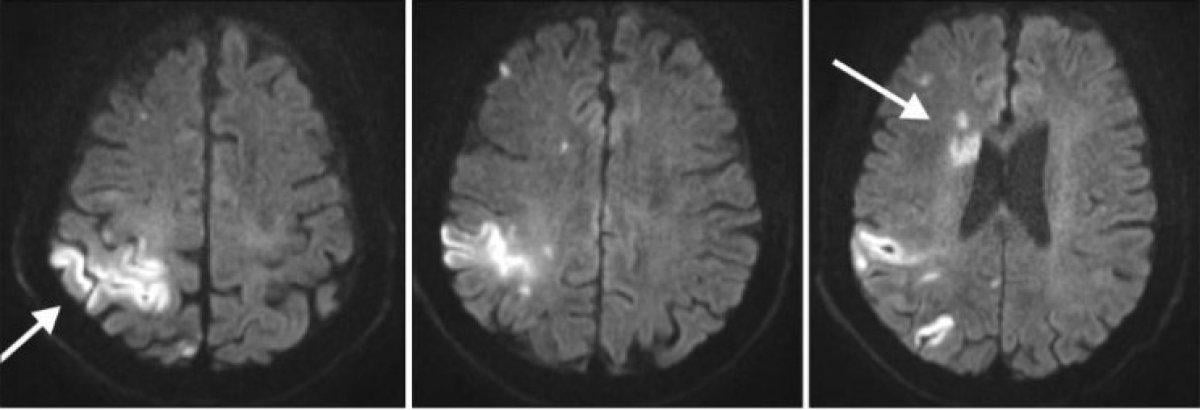

Psikiyatrik nedenlerden çok travma ve lezyonlardan kaynaklı olduğu da bilinmektedir.